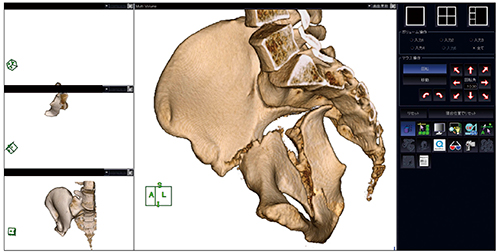

スキャンした患者のボリュームデータと,あらかじめスキャンしておいたインプラントのボリュームデータをVirtualPlaceのマルチボリューム機能から展開する。この時,「基準画像・重ね画像」に患者データを,「その他」にインプラントデータを登録する。展開されたVR画像から,カッティング機能やクリッピング機能を用いて目的の骨片を抽出する(図1)。

図1 目的の骨片を抽出